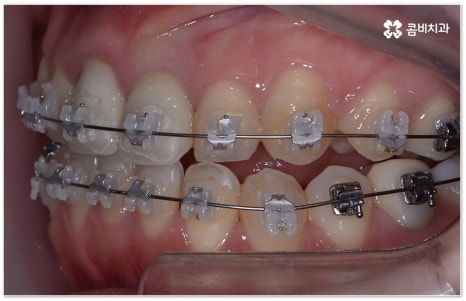

요즘 가장 많이 쓰이는 치아교정장치 인 클리피씨는 치아 색상의 세라믹 브라켓을 이용하기 때문에 심미성도 뛰어나고 자가결찰방식을 이용하여 보다 적은 힘으로 지속적이고 부드러운 치아 이동을 할 수 있도록 고안된 장치이므로 통증을 줄여줄 뿐 아니라 보통 2년 남짓 걸렸던 전체 교정 기간 역시 6개월 정도 감소시켜 줄 수 있습니다. 환자분들의 상황에 따라 내원 횟수 역시 줄일 수 있기 때문에 업무가 많이 바쁜 직장인분들의 경우에도 이용할 수 있다는 장점을 가지고 있어요.

부정교합을 개선할 때 교합이 어긋난 정도가 심하고 구조적인 원인이 커서 부분 교정이 아닌 전체 교정이 필요한 케이스인 경우라고 해도 말씀드렸던 클리피씨 교정 장치 또는 보다 심미성을 강조한 치아교정장치 들의 도움을 통해 다른 사람과 얘기를 하거나 음식을 먹을 때 브라켓이 두드러지게 드러나는 부담을 줄일 수 있으니 설측교정, 콤비교정, 투명교정, 인비절라인 등에 대해서 한 번 알아보시고 각자에게 맞는 방법으로 교정 치료를 시작해 보시길 권유드리고 있어요.